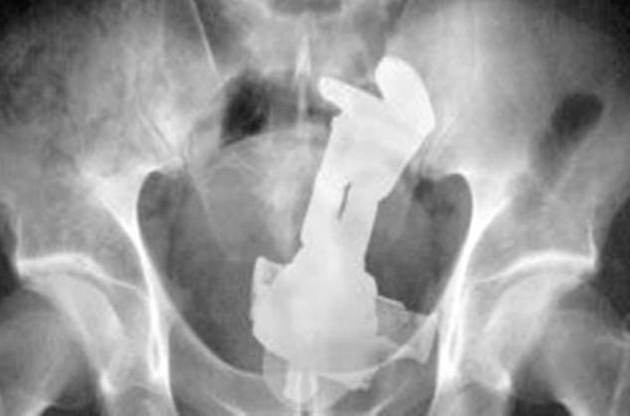

コンパクト(フィルム)カメラなんかが入っちゃった人が「じゃレントゲン撮影して調べますね」

「やめろ!中のフィルムが感光するじゃないか!」

なんて。

バズライトイヤーって 頭から入れた方が 入り易そうに思うが 出し易さを考えて 足から 入れたんだろうか

いや そんなこと まじめに 考えてもな